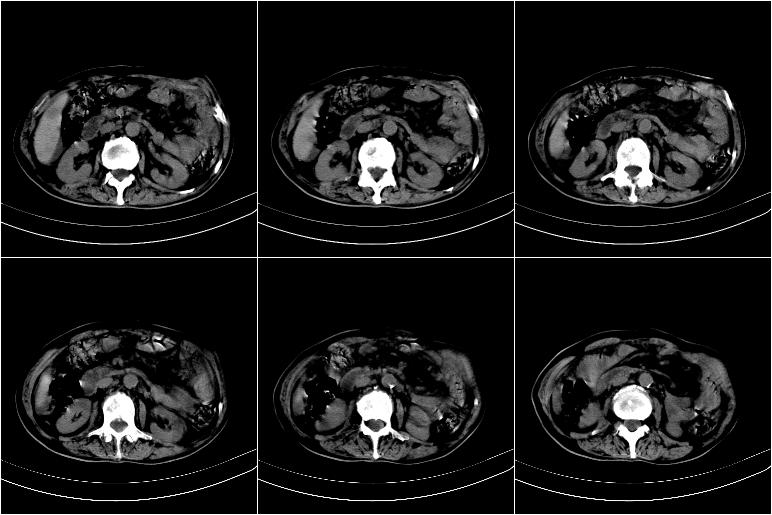

以下是引用边生丽在2009-8-17 11:43:00的发言:[br][br] [br] 右肺中心型癌伴右肺下叶不张、双肺转移并癌性淋巴管炎、心包和双侧胸腔积淮(转移?)、脑转移、肝转移、多骨(颅骨、椎骨)转移。 [br] [br]

以下是引用奥特之父在2009-4-20 19:58:00的发言:[br]支持胰腺癌并转移性病变。

以下是引用随光逐影在2009-8-17 14:09:00的发言:[br]支持 右肺中央型癌伴右肺下叶肺不张,纵隔淋巴结转移,双肺转移并癌性淋巴管炎,心包和双侧胸腔积液,脑转移、肝转移、多发性骨(颅骨、脊椎)转移。